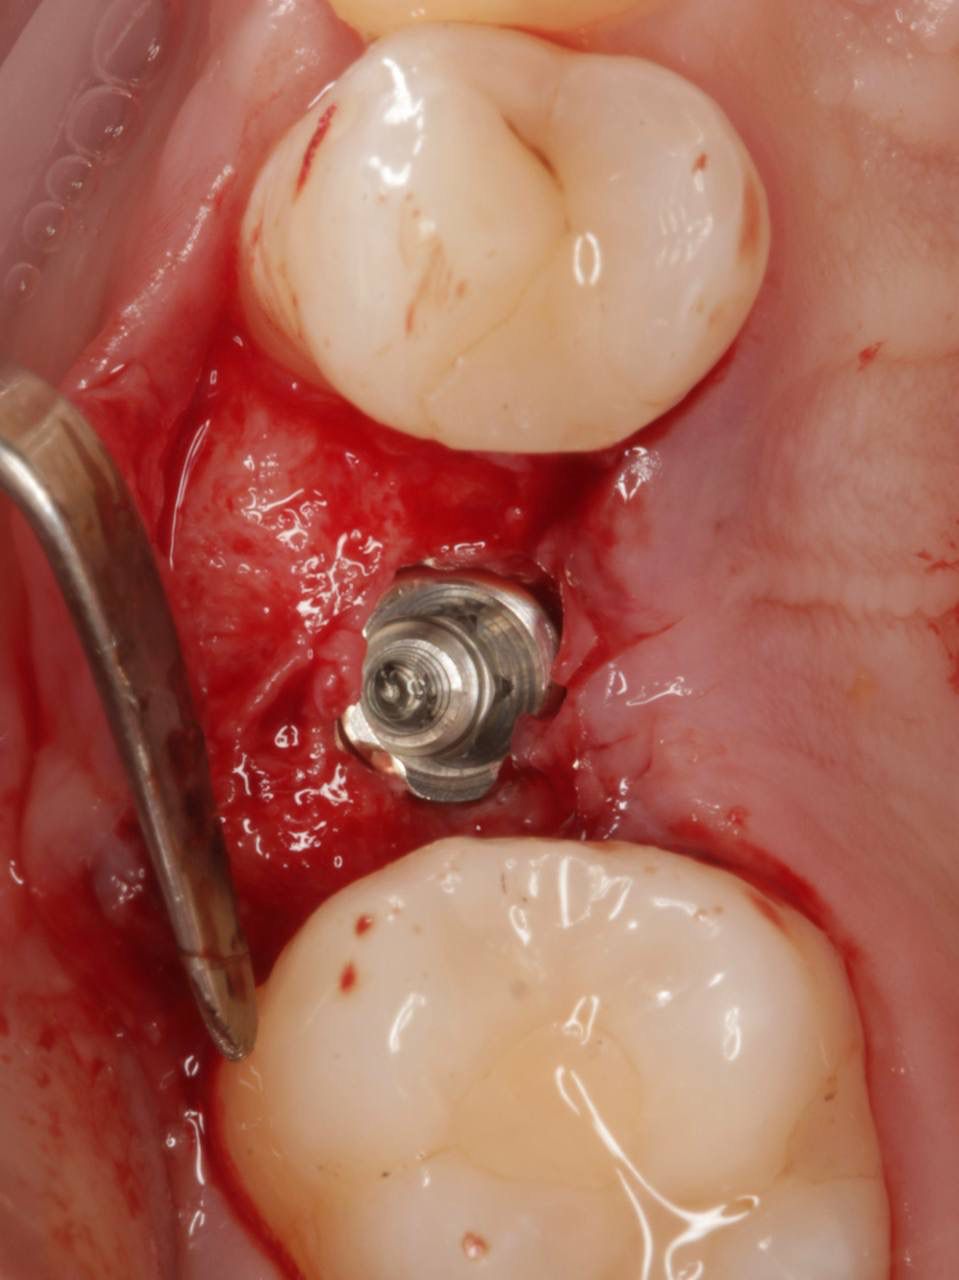

Установка импланта — Исламов Л.А.(10.11.2025)

Установка импланта, подшит трансплантат с бугра( для увеличения объема мягких тканей), установлен формирователь десны

Установка импланта